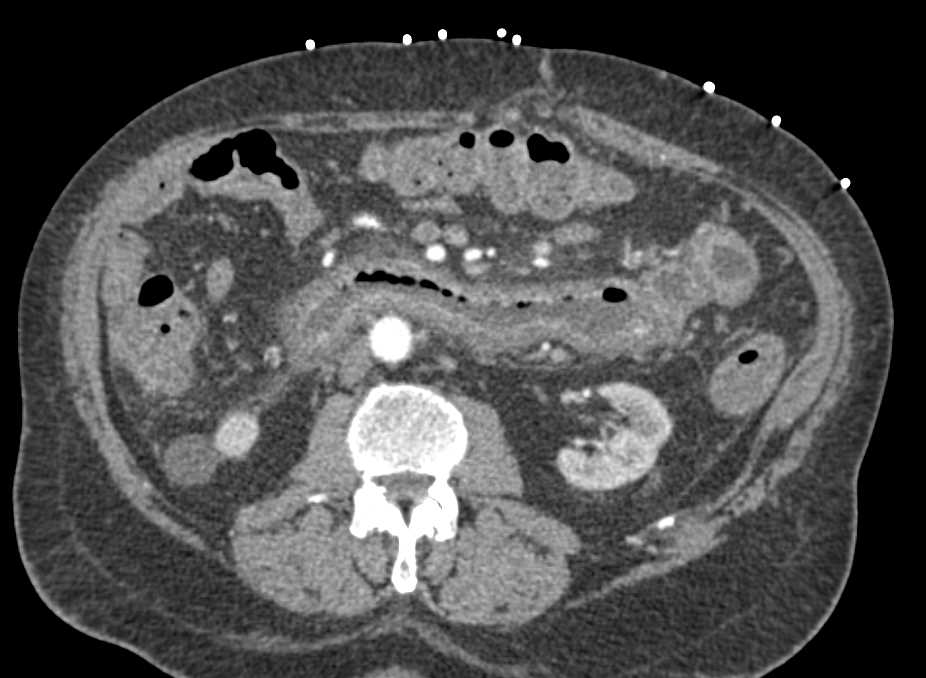

Small Bowel Obstruction due to a Distal Hernia in RLQ